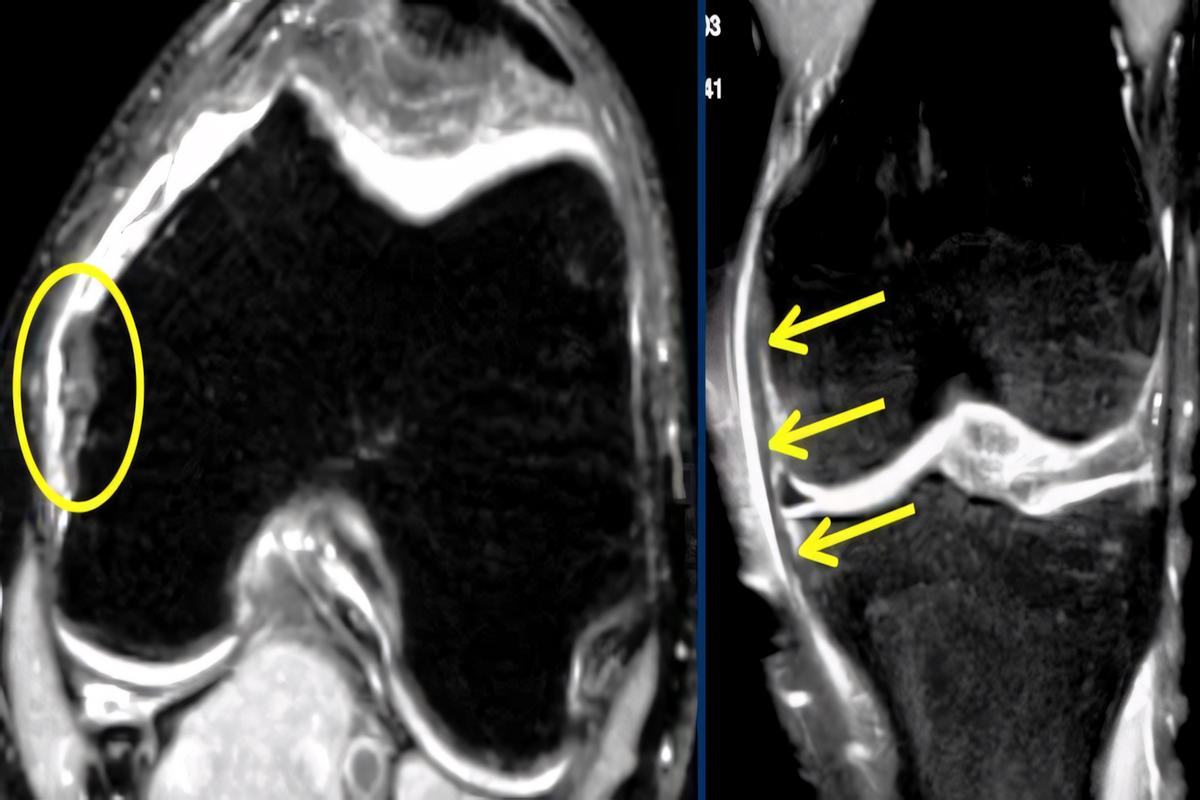

Ακτινογραφία γόνατος για αποκλεισμό κατάγματος ή αποσπαστικής βλάβης.

Μαγνητική τομογραφία (MRI), η οποία αποτελεί την πιο αξιόπιστη εξέταση για τον καθορισμό του βαθμού ρήξης και τον έλεγχο συνοδών κακώσεων (χιαστοί σύνδεσμοι, μηνίσκοι).

Η σωστή διάγνωση καθορίζει το θεραπευτικό πλάνο.